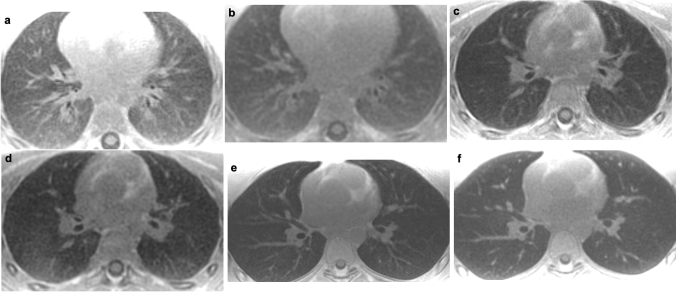

Qualitatively, both sequences show an increased lung parenchymal signal intensity in young children that decreases with increasing age (Fig. 3).

Fig. 3.

Comparison of the ultrashort echo-time (left column) and zero echo-time sequence (right column) depending on age in patients without lung pathology. a Axial slices at the hilum level of a 1-year-old boy and b, 4-year-old boy c and d and 17-year-old teenager e and f reveal signal change in lung parenchyma between 1 and 4 years of age for both sequences